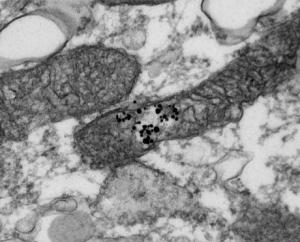

SIRT3 est une enzyme importante impliquée dans le métabolisme des graisses et la production d'énergie. Située dans les mitochondries du muscle squelettique humain, l'enzyme agit en ciblant certaines protéines et en modifiant leur activité. Mieux comprendre le rôle des enzymes situées dans les mitochondries, participe à trouver de nouvelles voies pour maintenir au mieux les fonctions cellulaires, la santé et la longévité. Ainsi, un déficit en SIRT3 a déjà été associé au risque de syndrome métabolique.

L'étude a été menée chez des jeunes hommes en bonne santé, répartis en 2 groupes : l'un a été soumis à un exercice d'endurance pendant une heure, l'autre au jeûne durant 48 heures. Les chercheurs ont ensuite prélevé des biopsies des muscles squelettiques à différents points dans le temps après l'exercice et le jeûne et isolé les mitochondries. Leur analyse constate que, bien que le niveau de SIRT3 diminue dans les cellules, sa situation dans la cellule n'est pas modifiée, ce qui suggère que son activité n'est pas régie par des modifications de niveau dans les mitochondries des cellules du muscle squelettique humain : en effet, les cellules musculaires squelettiques réagissent à des stimuli -comme l'exercice ou le jeûne- en activant de nombreuses protéines mitochondriales. La régulation de ces protéines se traduit par leur accès à certaines zones de la cellule. Les chercheurs s'attendaient donc à ce que SIRT3 se déplace vers les mitochondries en réponse à l'exercice et le jeûne, ce qui n'est pas le cas. Cependant, cette recherche montre que contrairement à d'autres protéines, SIRT3 ne semble pas régulée par des changements dans la localisation mitochondriale, en réponse au stress de l'énergie cellulaire dans le muscle squelettique humain.